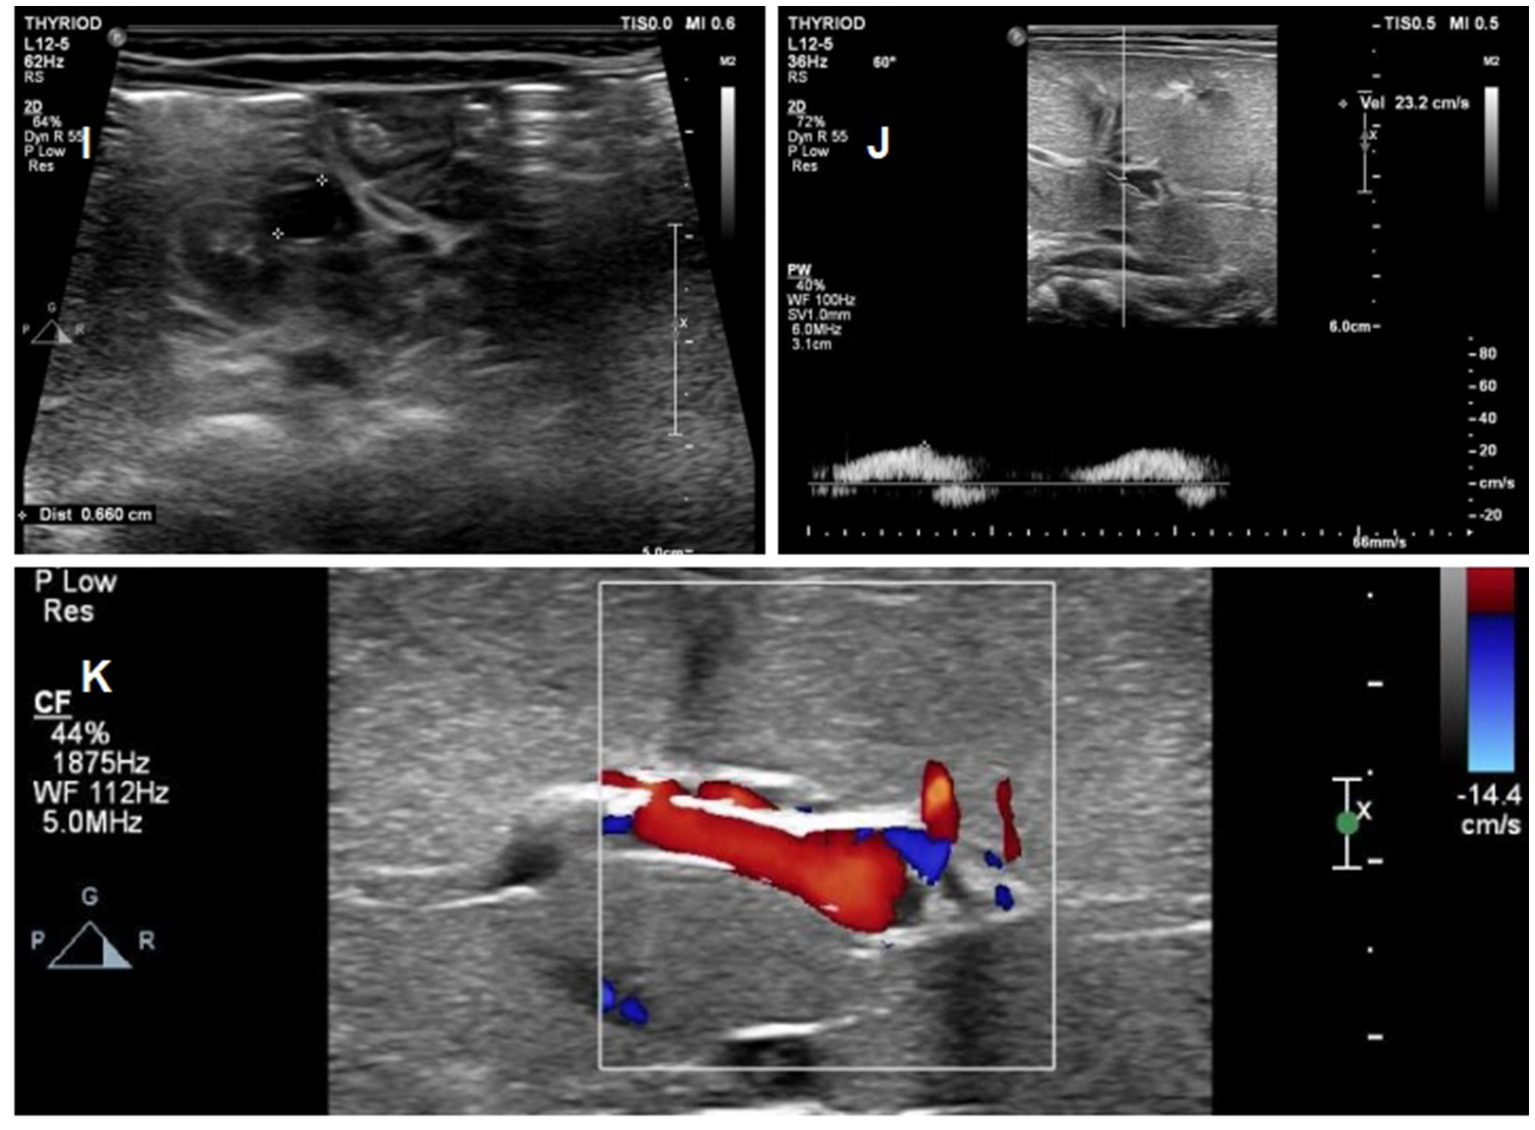

Figure 6

Ultrasound images of the patients on day 26 of life (I) Complete regression of the umbilical vein thrombus at day 26; (J) Complete regression of the portal vein thrombus at day 26; (K) normal blood flow signal of portal vein.